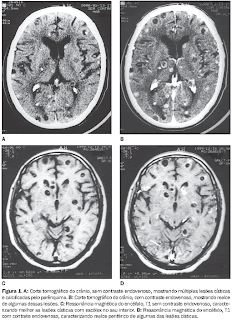

O

parasita intestinal Taenia solium,conhecido como solitária, do qual o porco é hospedeiro, é fácilmente

transmitido ao ser humano quando este ingere a carne suína, muitas vezes sem o

devido cuidado do adequado cozimento. Esses parasitas tem afinidade pelo tecido

cerebral, onde se alojam ou seus ovos podem chegar ao cérebro através da

corrente sanguínea.Nesses casos podem simular um ataque epiléptico que

entretanto não é real, mas decorrente de uma alteração inflamatória do tecido

cerebral, reacional a presença do corpo estranho lá alojado. Mesmo em países

desenvolvidos onde a presença da doença praticamente não existe, estudos

alertam para a necessidade da atenção médica no momento de fechar o

diagnóstico, principalmente quando tratar-se de paciente oriundo da América

Latina, Ásia e África. É o que relata a Revista de Neurologia de 16/01/2013.

Neurocisticercosis

pediátrica: a propósito de dos casos.

[REV NEUROL 2013;56:86-90] PMID: 23307354 - Nota Clínica - Fecha de publicación:

16/01/2013

Introducción.

La neurocisticercosis es la enfermedad parasitaria más frecuente del sistema

nervioso central y está causada por una infestación por la larva de la Taenia solium.

Se trata de una enfermedad endémica en los países en vías de desarrollo,

principalmente de América Latina, Asia y África, mientras que su presencia en

Europa es anecdótica. Casos clínicos. Presentamos los casos de dos niños de

origen no español, que comenzaron con una crisis epiléptica y que fueron

diagnosticados inicialmente como tumores cerebrales primarios. Ambos fueron

intervenidos quirúrgicamente y al diagnosticarse la parasitosis, recibieron

posteriormente tratamiento antiparasitario. Conclusiones. La neurocisticercosis

es una causa potencial de epilepsia incluso en aquellos países en los que no

endémica. Numerosos casos presentan dificultades en el diagnóstico y se pueden

confundir con otras lesiones intracraneales. Los facultativos debemos estar

alerta, ya que se trata de una patología con un cierto repunte en España y se

debe tener en cuenta en los diagnósticos diferenciales cuando tratamos

pacientes procedentes de América Latina o África.

Introdução.

A neurocisticercose é uma doença parasitária freqüente do sistema

nervoso central e é causada por uma infestação de larvas de Taenia solium. É

uma doença endêmica em países em vias de desenvolvimento, principalmente na

América Latina, Ásia e África, enquanto na Europa chega a ser motivo de piada

apesar disso podem surgir casos que merecem ser bem diagnosticados por se

confundir com epilepsia. O estudo mostra dois casos de duas crianças de origem

não-espanhola, que iniciou com convulsão e que inicialmente foram

diagnosticados como tumores cerebrais primários. Ambos foram operados e diagnosticou-se

infecção parasitária que foi posteriormente tratado com antparasitário. Os

autores concluem que a neurocisticercose é uma causa potencial de epilepsia,

mesmo em países onde não é endêmica. Inúmeros casos apresentam dificuldade de

diagnóstico e põem ser confundidos com outras lesões intracaranianas. O médico

deve estar alerta, uma vez que é uma patologia com grande repercursão na

Espanha e deve ser considerada no diagnóstico diferencial, ao se propor

tratamento para pacientes da América Latina ou África.